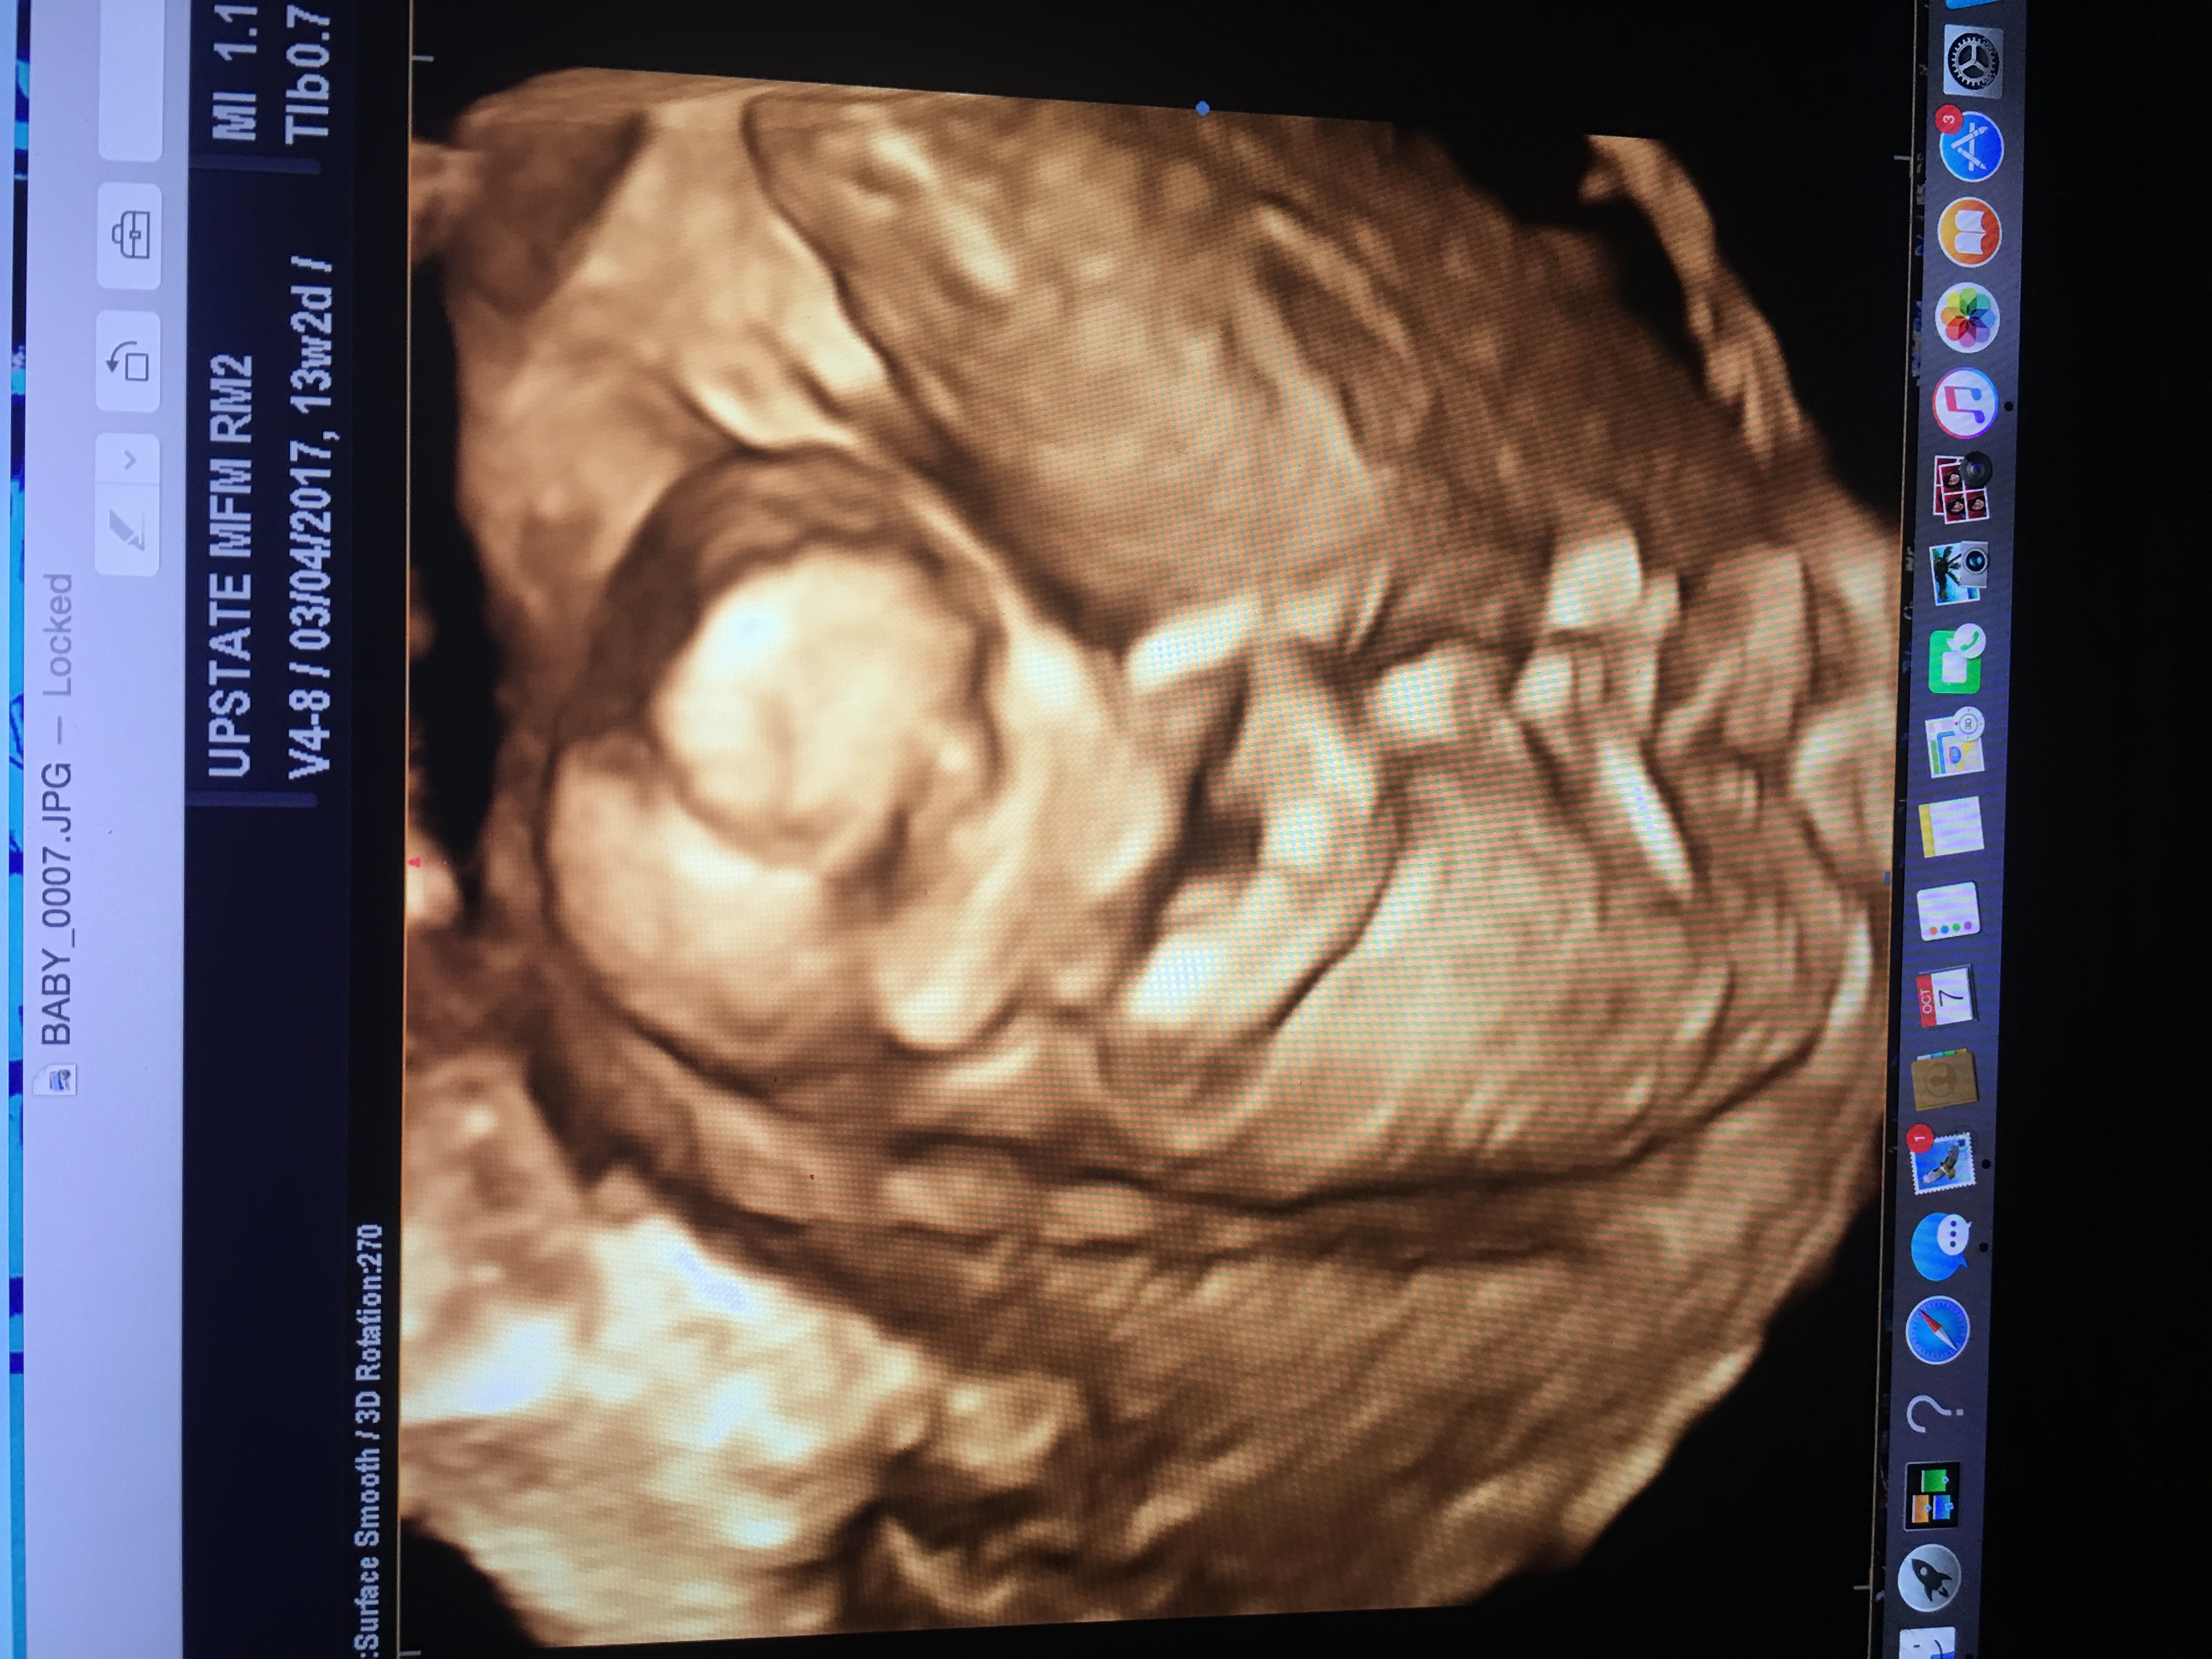

Attachment 35007

Maybe boy. Any 2D pics?

We didn't want to find out the sex so the only other pics are of face in 2d. These were the only full body ones we got. Just curious if anyone had any good guesses :)

It looks to me like a boy nub sticking out there, so I guess boy :)